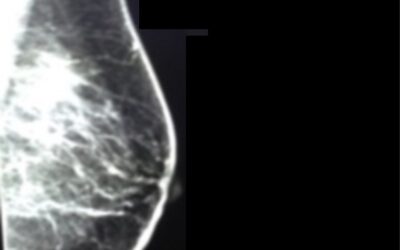

Breast Cancer, Early Detection, and You

This past Tuesday I went for my annual mammogram. When I entered the waiting room, the staff member facing me was the nurse who crawled into the hospital bed with me on one of my darkest nights following the birth and subsequent death of my son. In my memoir, Digging...